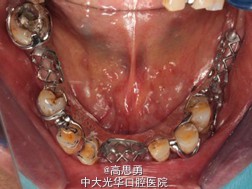

7、试戴 检查义齿的就位、固位可,无翘动,咬合关系正确,利用咬合纸检查,上下颌尖窝接触均匀全面,抛光,患者表示满意,嘱注意事项,定期复诊。

最终治疗方案:根据患者的年龄、身体状况、治疗周期、经济状况,患者最终选择方案5,即#13RCT后树脂充填,上颌结合卡环式可摘局部义齿修复;下颌可摘铸造支架式局部义齿修复。

病历发表的很认真,很详细,双侧或者单侧游离缺失,传统三臂卡修复对基牙扭力很大,楼主这方面考虑的很周到,在游离端缺失都选择了RPA或者RPI卡环,改变义齿支持模式...查看全部